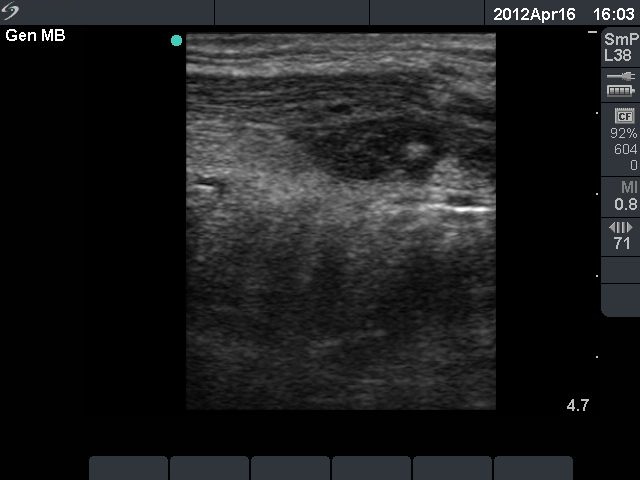

Third row: 3 days after the fourth session of ethanol treatment - the cyst became more enlarged and painful. The body temperature rose to 38.2 C, the erythrocyte sedimentation rate was 50 mm/H.

Ultrasonography: the size of the nodule was 30x25x34 mm, and another hyperechogenic lesion was found dorsal to the treated lesion.